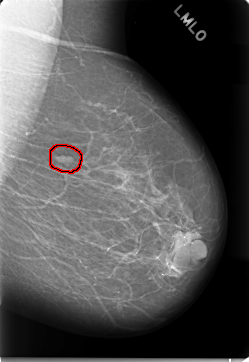

FILE: C_0019_1.LEFT_MLO.OVERLAY

TOTAL_ABNORMALITIES 1

ABNORMALITY 1

LESION_TYPE MASS SHAPE OVAL MARGINS CIRCUMSCRIBED

ASSESSMENT 2

SUBTLETY 5

PATHOLOGY BENIGN

TOTAL_OUTLINES 1

BOUNDARY